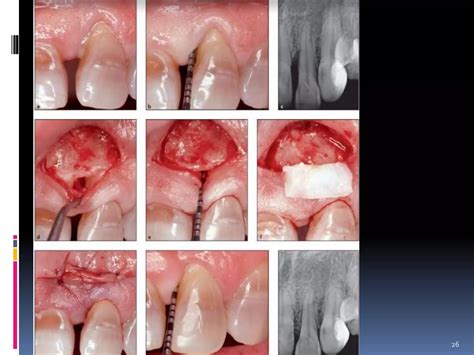

Bone Grafts | Allograft Academy